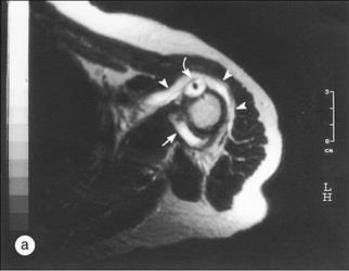

PMR病人的T2加权图:箭头所指肩峰下和三角肌下滑囊炎、肱二头肌腱炎症